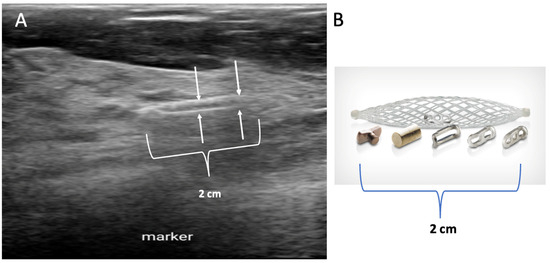

Biopsy site markers come in many shapes and sizes, but most measure less than 10 mm in length. In breast radiology, the most commonly used biopsy site markers are metallic (stainless steel, titanium, or nickel) devices that are optimized for detection by mammography, but are poorly visible by ultrasound. However, several biopsy site markers have been optimized for ultrasound detection by encasement of the metallic component in a larger, absorbable collagen or hydrogel sleeve (Figure 6). For cancers that are already visible by ultrasound, the type of marker is unimportant as the tumor itself provides an obvious target for ultrasound-guided cryoablation. However, when the breast cancer is very small or invisible to ultrasound, insertion of an ultrasound-visible marker at the time of the initial needle biopsy or subsequently will facilitate ultrasound-guided cryoablation of ultrasound-occult cancer.

Figure 6.

Ultrasound image (A) showing an example of a 2 cm long, basket-like, tubular, ultrasound-visible biopsy site marker (bracketed by paired arrows) that documents the location of ductal carcinoma in situ, which itself was not ultrasound visible. Image (B) shows an enlarged view of an actual basket-like marker and the shapes of various radio-opaque markers they may contain.

Generally, a single biopsy site marker is sufficient for marking the site of most breast cancers. However, patients with a wide span of disease may benefit from placement of two or more ultrasound-visible markers to outline or bracket the borders of the cancer to improve targeting of the cryoablation treatment (Figure 7).